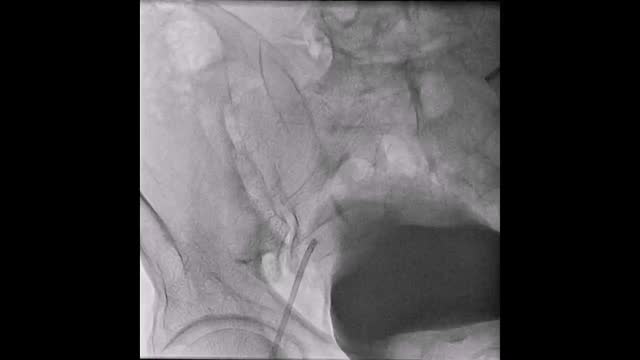

El paciente se traslada a la sala de hemodinamia donde se intenta la extracción del dispositivo. Se utilizan diferentes catéteres lazo de 10, 25 y 30 mm, así como lazos de fabricación con guías largas y cortas intentando movilizar el dispositivo desde diferentes accesos vasculares (acceso bifemoral 6 y 18 Fr y radial 6 Fr) (figuras de la 1 a la 4). Se produce como complicación disección de aorta abdominal con extensión a arteria ilíaca común derecha (figuras 5 y 6) y pérdida total del flujo en extremidad inferior ipsilateral con signos y síntomas de isquemia arterial aguda, por lo que el paciente es trasladado de forma urgente al quirófano de angiología y cirugía vascular. Se realiza disección de aorta abdominal infrarrenal vía laparotomía media con aortotomía longitudinal en el lugar de la localización del cuerpo extraño visualizándose el dispositivo migrado anclado a la íntima-media de la pared arterial. Se procede a su extracción y posteriormente se realiza cierre de aortotomía con parche de pericardio bovino fijando la disección y corrigiendo así el defecto (figuras de la 7 a la 9). El paciente sale de quirófano con pulso pedio bilateral y excelente perfusión distal.